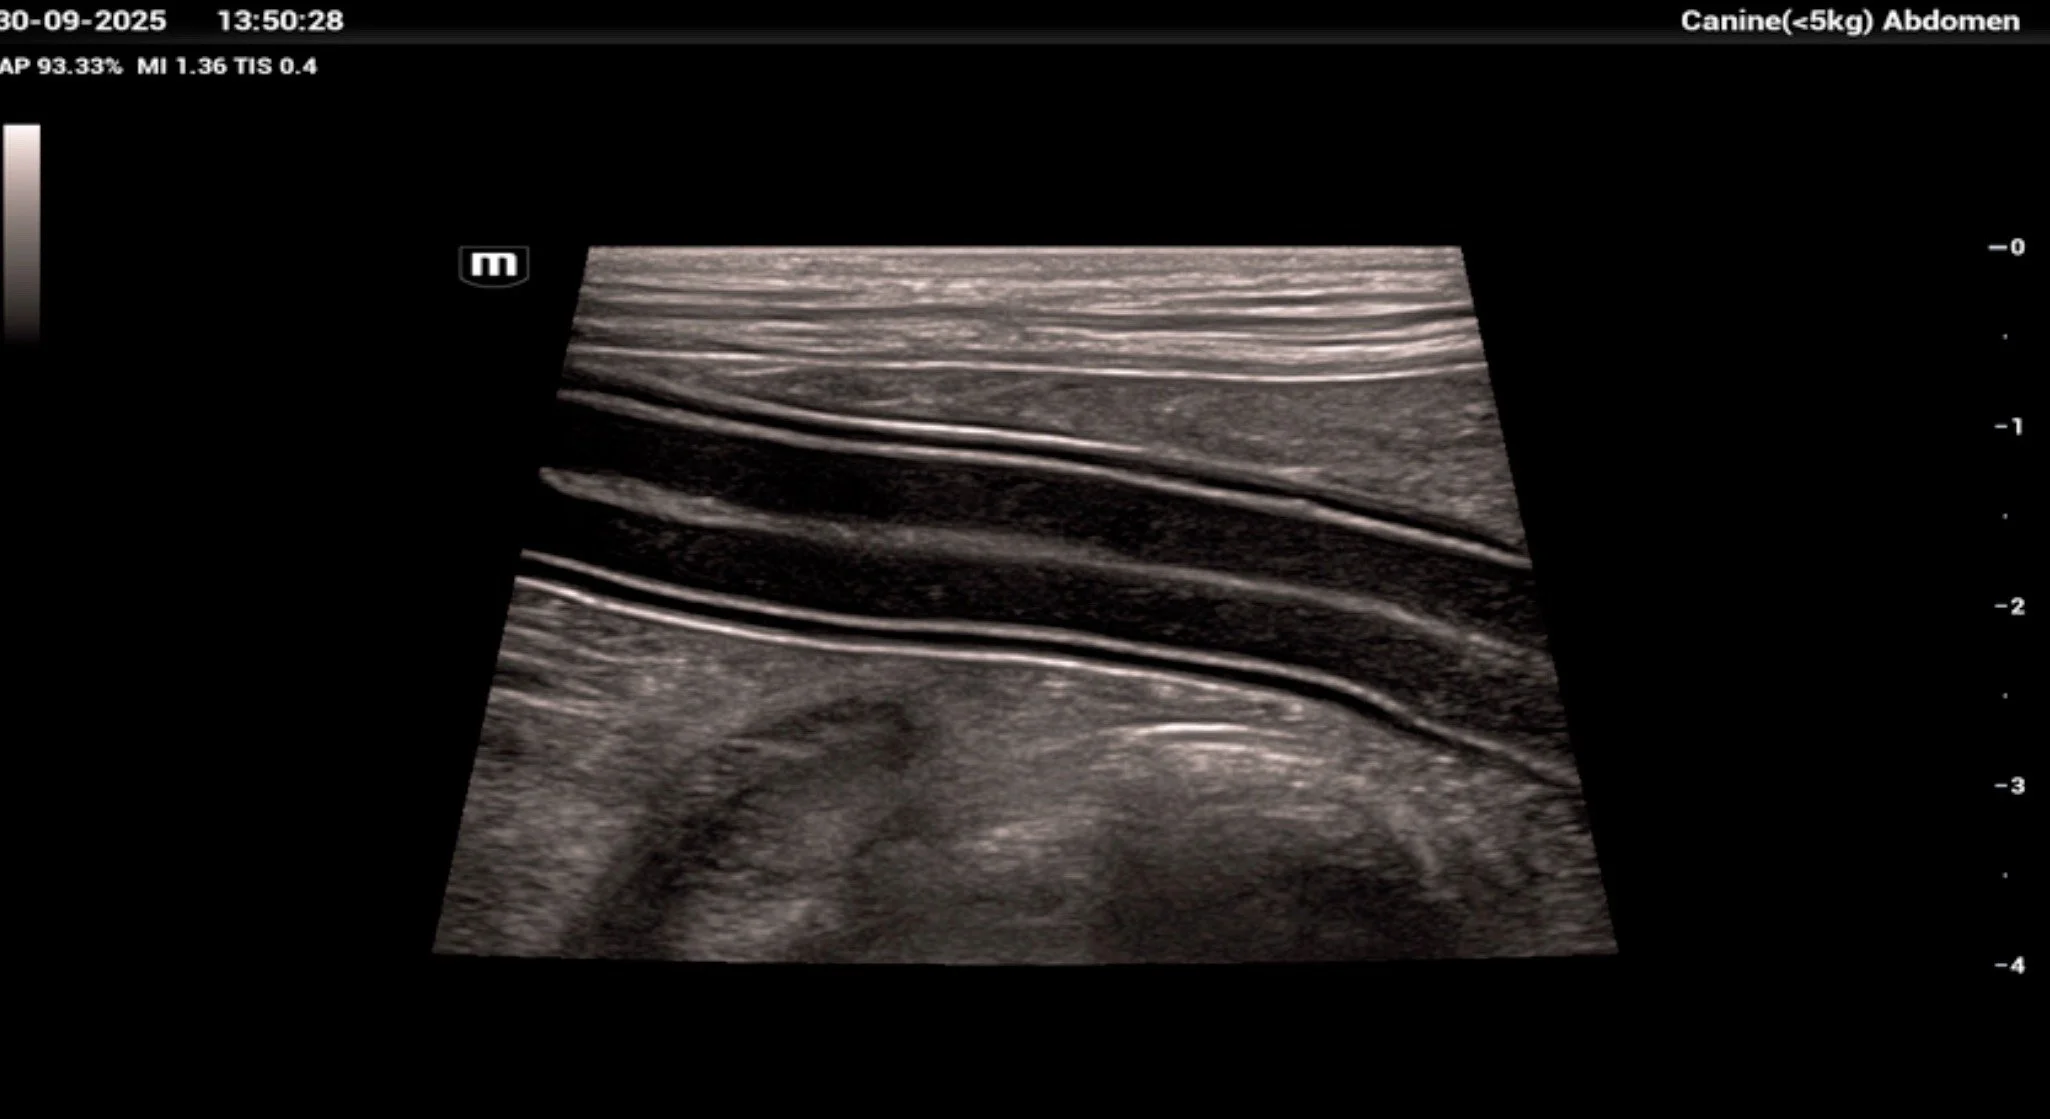

High-resolution ultrasonographic image of canine jejunum demonstrating all five histological layers: mucosal interface, mucosa, submucosa, muscularis externa, and serosa. The clarity of stratification supports normal architecture and provides a baseline for comparison in cases of enteritis, lymphangiectasia, or neoplasia.

The small intestine of dogs and cats—comprising the duodenum, jejunum, and ileum—shares a conserved four-layered histological architecture: mucosa, submucosa, muscularis externa, and serosa. Despite this overarching similarity, each segment exhibits distinct structural and functional adaptations that reflect its role in digestion, absorption, and immunological surveillance. Understanding these differences is essential for interpreting diagnostic imaging, histopathology, and surgical anatomy in clinical practice.

In the duodenum, the mucosa is characterized by tall, leaf-like villi and deep crypts of Lieberkühn. The villi are more robust proximally, reflecting the duodenum’s role in nutrient emulsification and early absorption. The jejunum displays long, finger-like villi with a high surface area-to-volume ratio, optimized for maximal nutrient absorption. In contrast, the ileum exhibits shorter, blunter villi and a higher density of goblet cells, consistent with its role in water and electrolyte absorption and mucosal protection.

This layer consists of two smooth muscle layers: an inner circular and an outer longitudinal layer, separated by the myenteric (Auerbach’s) plexus. This arrangement is consistent across all three segments and is responsible for peristalsis and segmental contractions. In dogs and cats, the muscularis externa is relatively uniform, although subtle regional differences in thickness and innervation density may exist. The jejunum, for example, may exhibit slightly more prominent segmentation activity, reflected in the rhythmic contraction patterns observed during ultrasonography.